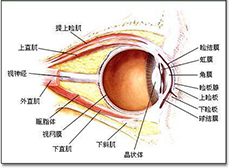

带状疱疹病毒性睑皮炎

疾病介绍:本病是由带状疱疹病毒感染三叉神经半月神经节或三叉神经第一支所致,多见于老年人或体弱者。多有发热、乏力、全身不适的前驱症状。随后病变区出现剧烈…【详细】

单纯疱疹病毒性角膜炎

疾病介绍:单纯疱疹病毒性角膜炎是由单纯疱疹病毒( HSV)引起的角膜感染,患者多为复发性感染病例。原发性单纯疱疹病毒感染常在幼儿阶段,多表现为急性滤泡性结…【详细】

睑板腺梗塞(结膜结石)

疾病介绍:睑板腺梗塞是睑板腺排泄管闭塞,分泌物积存日久钙化形成小结石。睑结膜下可透地黄色沉着物。一般尤不适。当小结石的尖锐棱角突出于结膜面时,则引起异…【详细】

睑板腺囊肿(霰粒肿)

疾病介绍:睑板腺囊肿足睑板腺排出口阻塞,腺体分泌物潴留在睑板内,对周围组织产生慢性刺激而引起的特发性无菌性慢性肉芽肿性炎症。多见于青少年或中年人。一般…【详细】